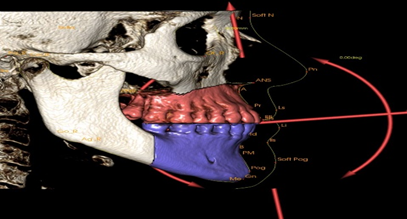

| - Ứng dụng trong chỉnh nha: Với phim chụp CBCT, bác sĩ chỉnh nha có thể coi tình trạng răng ngầm, hướng mọc của các răng, tương quan và sự phát triển xương hàm, vị trí xương để đặt minivis, phân tích các thông số chỉnh nha về thẩm mỹ khuôn mặt, đánh giá kết quả trước và sau khi chỉnh nha của bệnh nhân. | | |